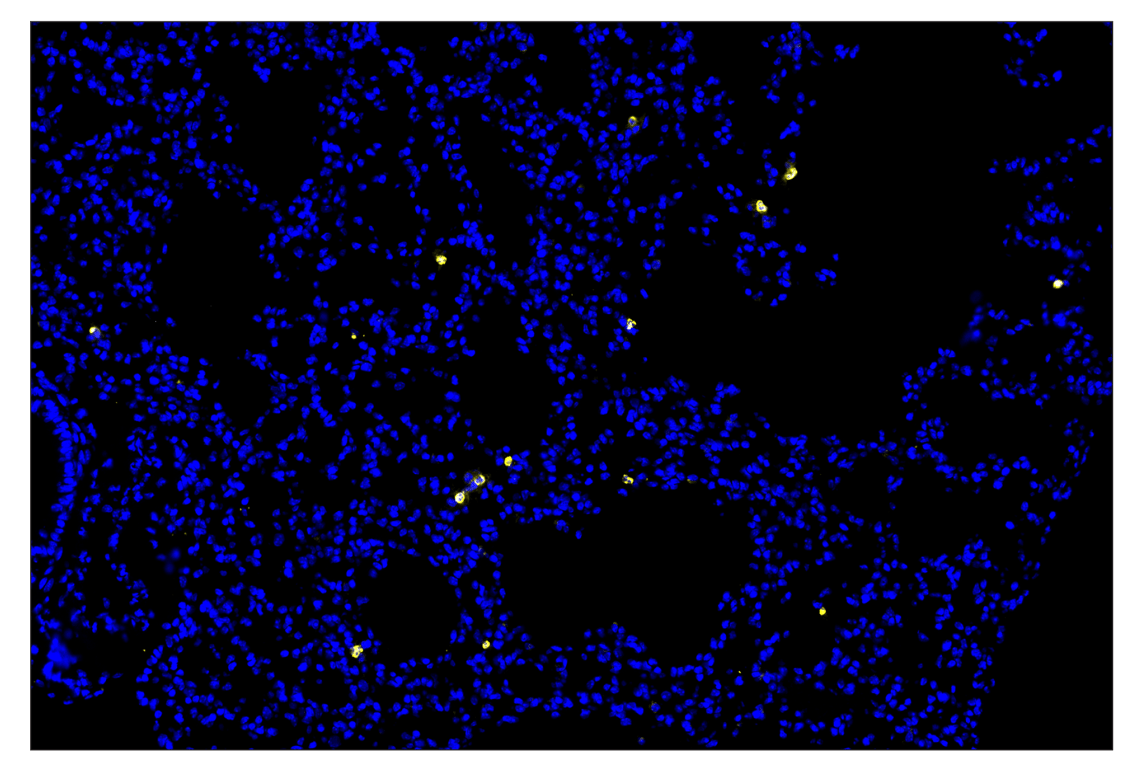

Eosinophil cationic protein (F3G7N) & CO-0230-488 SignalStar® Oligo-Antibody Pair

| Eosinophil cationic protein (F3G7N) Rabbit Monoclonal Antibody (SignalStar® Conjugate 0230) | 53231 | 50 µl | M | Rabbit IgG |

| Complementary Oligo (CO-0230-488) | 75688 | 30 µl |

SignalStar Oligo-Antibody Pairs are compatible with the SignalStar Multiplex IHC Buffer Kits for use in fluorescent multiplex imaging experiments. This product includes the oligo-conjugated antibodies and complementary oligos required for labeling your target protein on up to 10 slides. SignalStar Multiplex IHC Buffer Kits are required to amplify and image the target signal. Multiple oligo-antibody pairs can be conveniently combined into a multiplex panel using the SignalStar Multiplex IHC Panel Builder. SignalStar Multiplex IHC Kits & Reagents are not compatible with all of Cell Signaling Technology® products and protocols that are recommended for use in immunohistochemical assays.